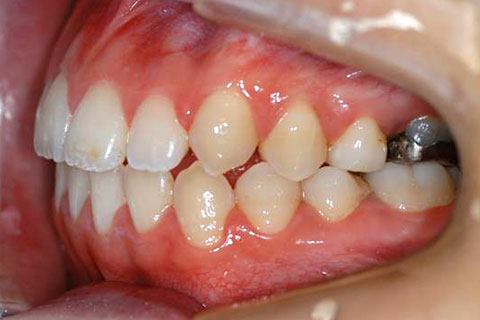

治療前

治療後